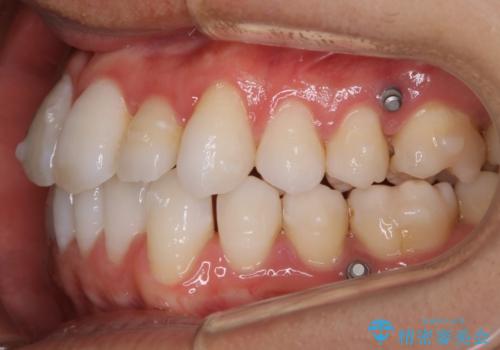

- マウスピース(インビザライン)

- 88万円+TAX(マイクロインプラント費用込み)費用は治療当時の料金となります